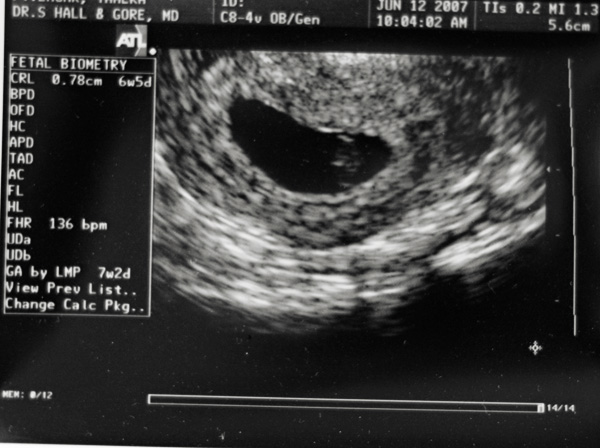

We are expecting another Baby Eagar! I am due at the end of January. The ultrasound below was taken at my first Doctor’s visit in June. It is always so reassuring to see the little bean. You can barely see it, but the little white line on the bean is the heartbeat! I had another appointment today, and the heartrate was 160 bpm! Kyla thought it was fun to listen to the heartbeat, however, she was a bit nervous when we were walking back to the exam room. I had to reassure her that we were there for me and not for her!